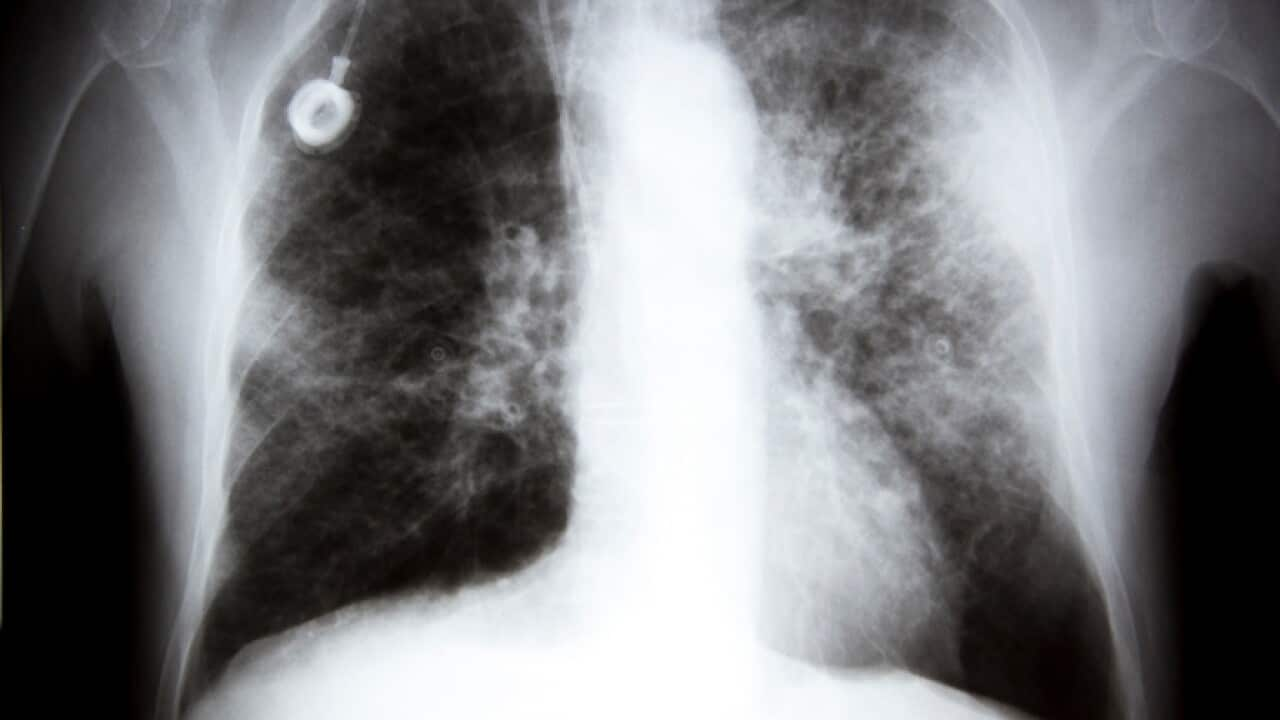

An X-ray showing lung cancer Source: Getty

ការពិនិត្យរកមើលរោគវិនិច្ឆ័យជំងឺមហារីកសួតត្រូវបានគេមើលឃើញថាមានតំលៃថ្លៃពេក ហើយពេលខ្លះមិនអាចជឿទុកចិត្តបាន។ ប៉ុន្តែបច្ចុប្បន្ន ជំងឺនេះត្រូវបានគេទទួលស្គាល់ថា ជាប្រភេទមហារីកដែលឆក់យកជីវិតមនុស្សច្រើនបំផុតនៅក្នុងប្រទេសអូស្ត្រាលី។